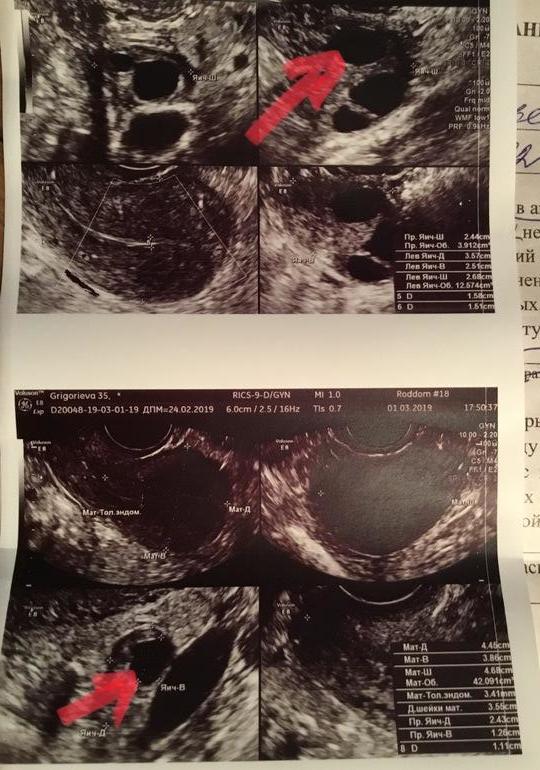

Я регулярно веду графики БТ. Циклы были как по часам всю жизнь. После 30 лет циклы были по 26-27 дней с О на 13-14дц и второй фазой в 12 дней. И так я беременела с первых попыток аж три раза подряд. Последняя беременность увы, неудачная. И вот, после выскабливания у меня уже пятый цикл начался. Три последних стали с ранней О ( на 9-11 дц) и с второй фазой в 14 дней. Ну ладно, всякое бывает, организм, видимо, включил турборежим. Но вот беда, все эти три цикла были пролетные. Последний февральский цикл прям красив был как никогда, судя по графику БТ, но пролетный всё равно. В этом цикле М начались с нехарактерной мне небольшой коричневой мазни. Но ещё в конце прошлого цикла, я для себя решила, что если он будет пролетным, я схожу на УЗИ сразу после М и проверю состояние своих женских органов. И вот сегодня, то ли 5 дц, то ли 6 дц(если считать небольшую мазню перед нормальными М), сходила… сижу у кабинета, жду очереди и считаю, что если у меня снова будет ранняя О на 10 дц примерно, то сейчас должен быть уже виден доминантный фолик как минимум 12 мм. А узистка смотрит сначала левый, там всё хорошо и ДФ - 19мм(УЖЕ!!!), а потом правый, а там их вообще три и один уже 18,6 мм 😳😳😳😳😳. Что происходит?! Я даже о сексе с мужем не успела подумать, потому что только-только закончились М, прям с утра ещё были розовые выделения, а уже О грядёт. Ну так вот, а эндометрий то только 3,4 мм. Успеет ли что-то нарасти? И как помочь то теперь моей маточке что-то нарастить? 🤯

И фото моих красивых органов 🧐